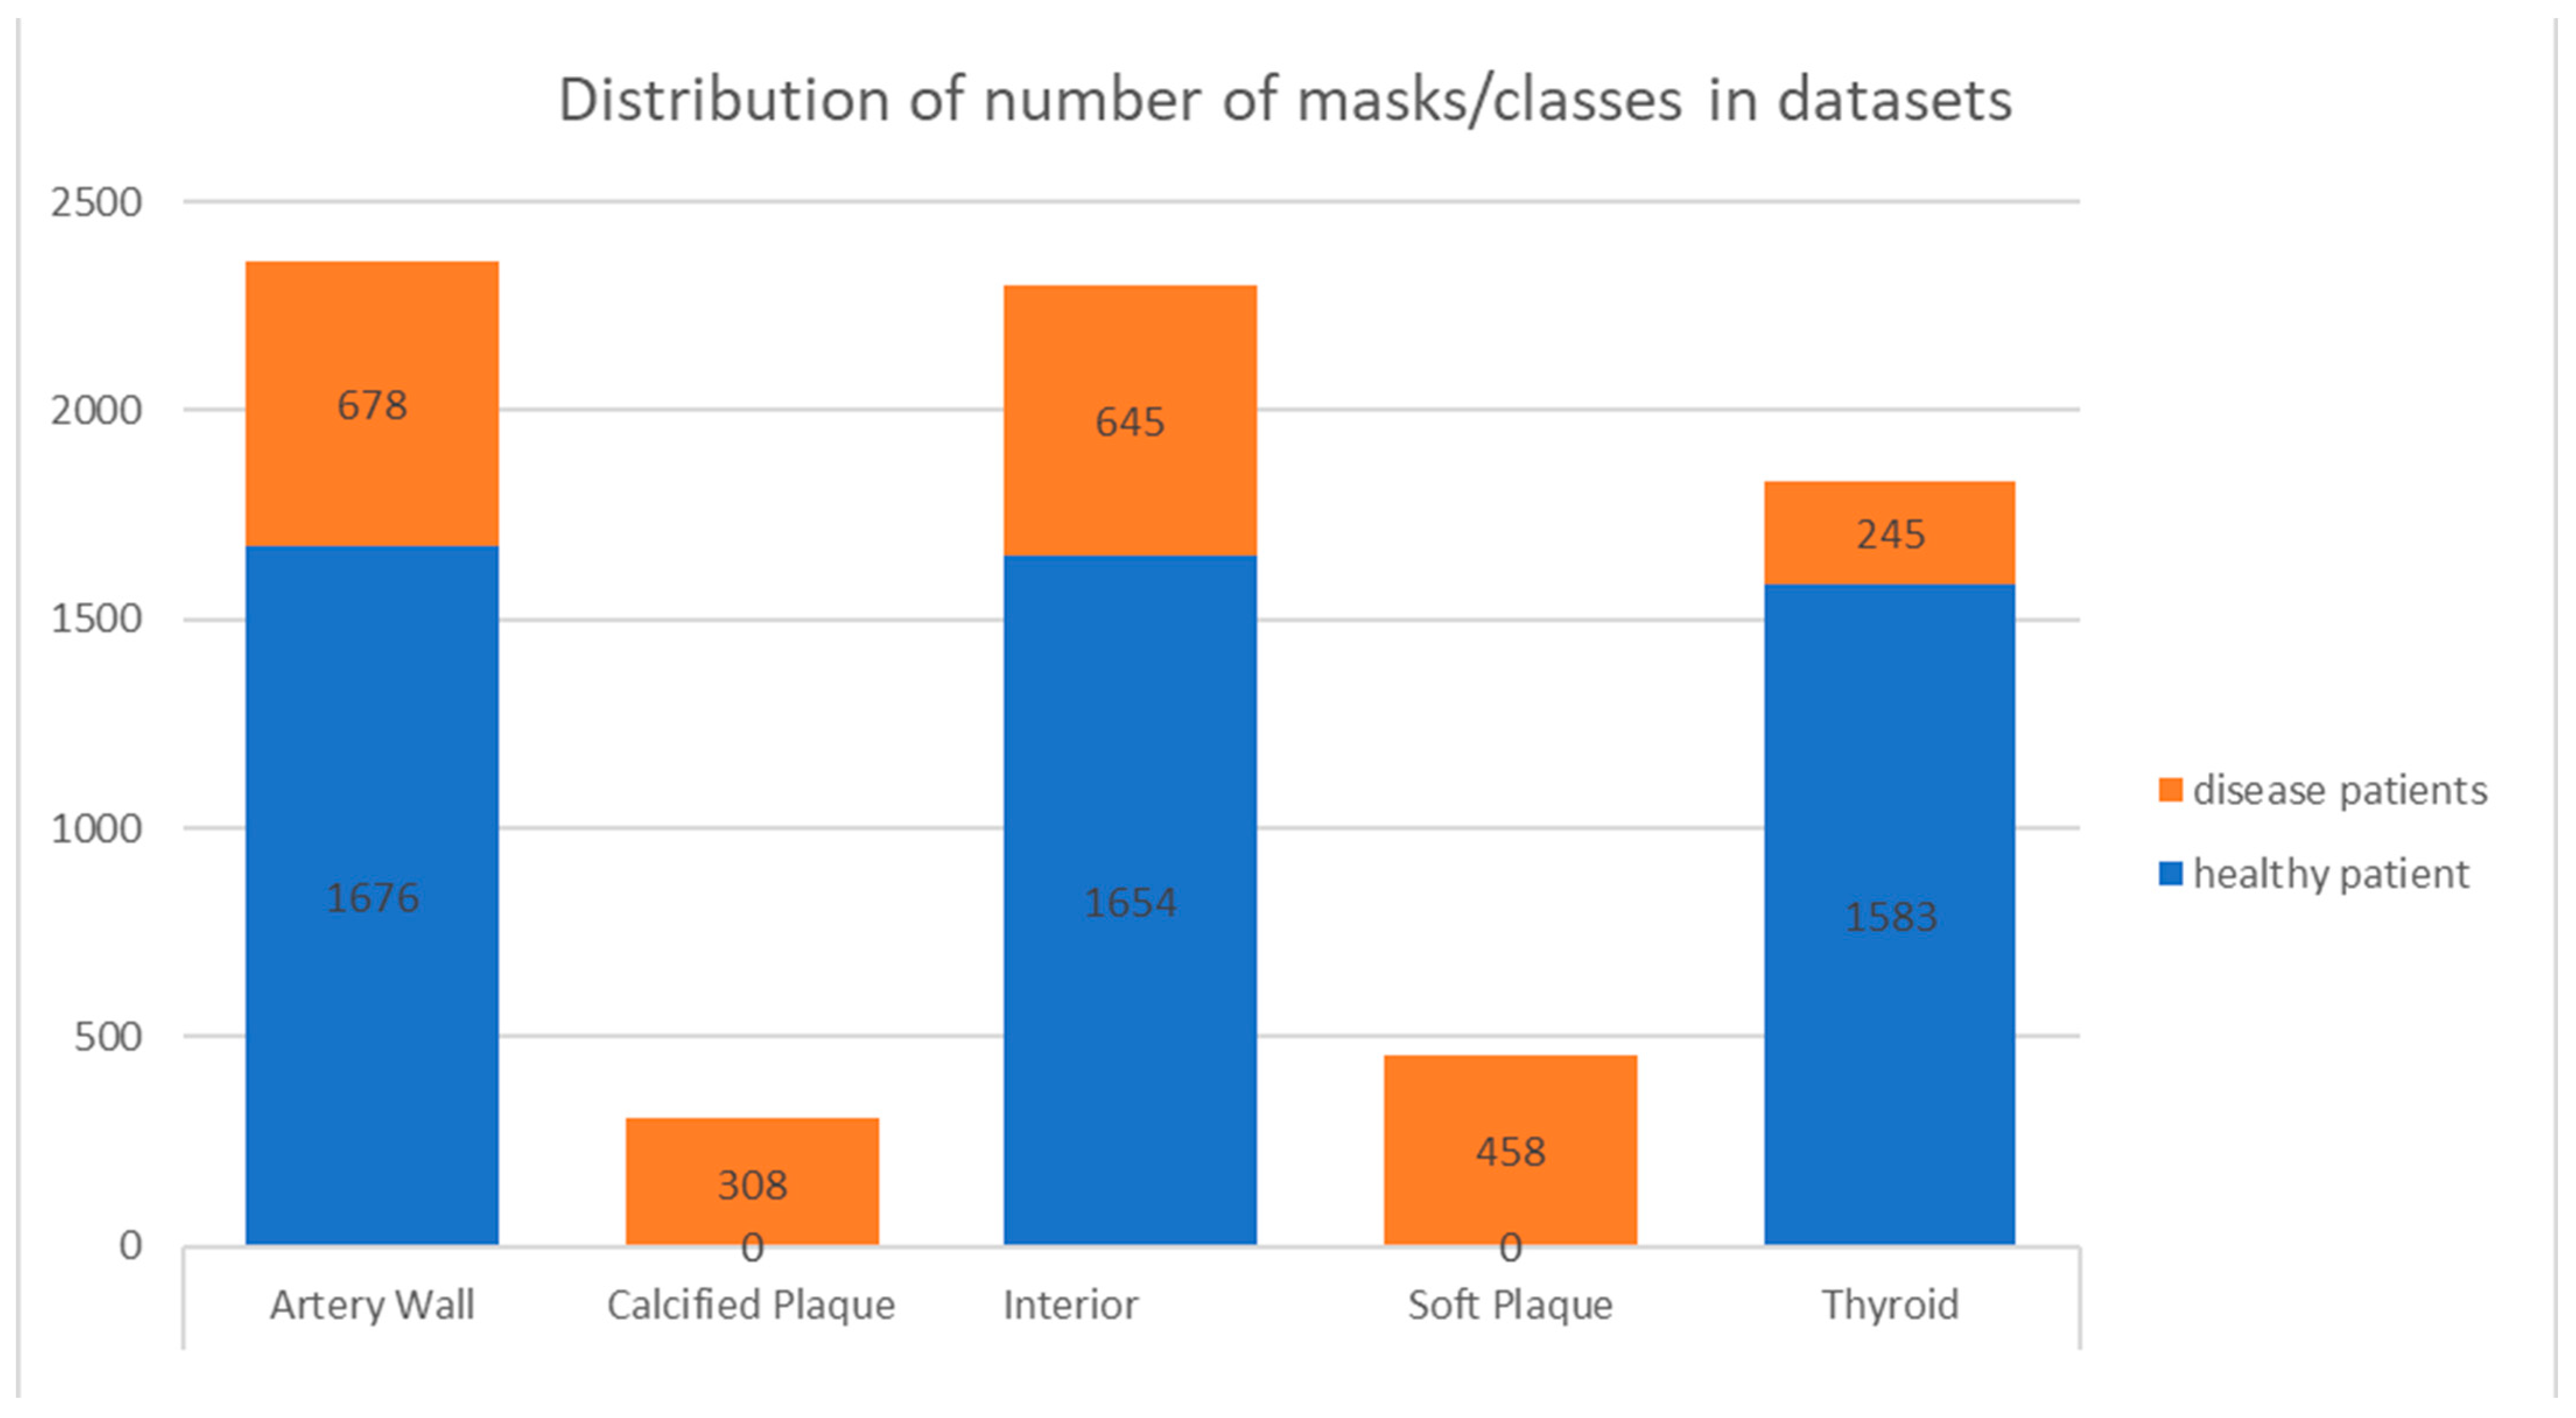

2.5. Machine-Learning Dataset Preparation

3.1. 2D Automatic Segmentation